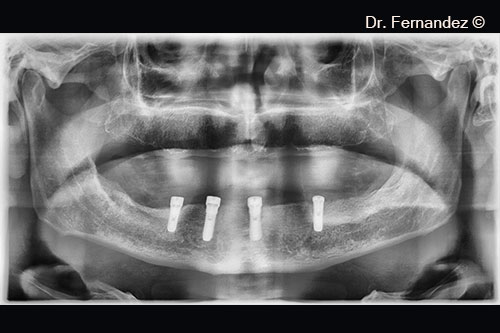

Initial radiological appearance